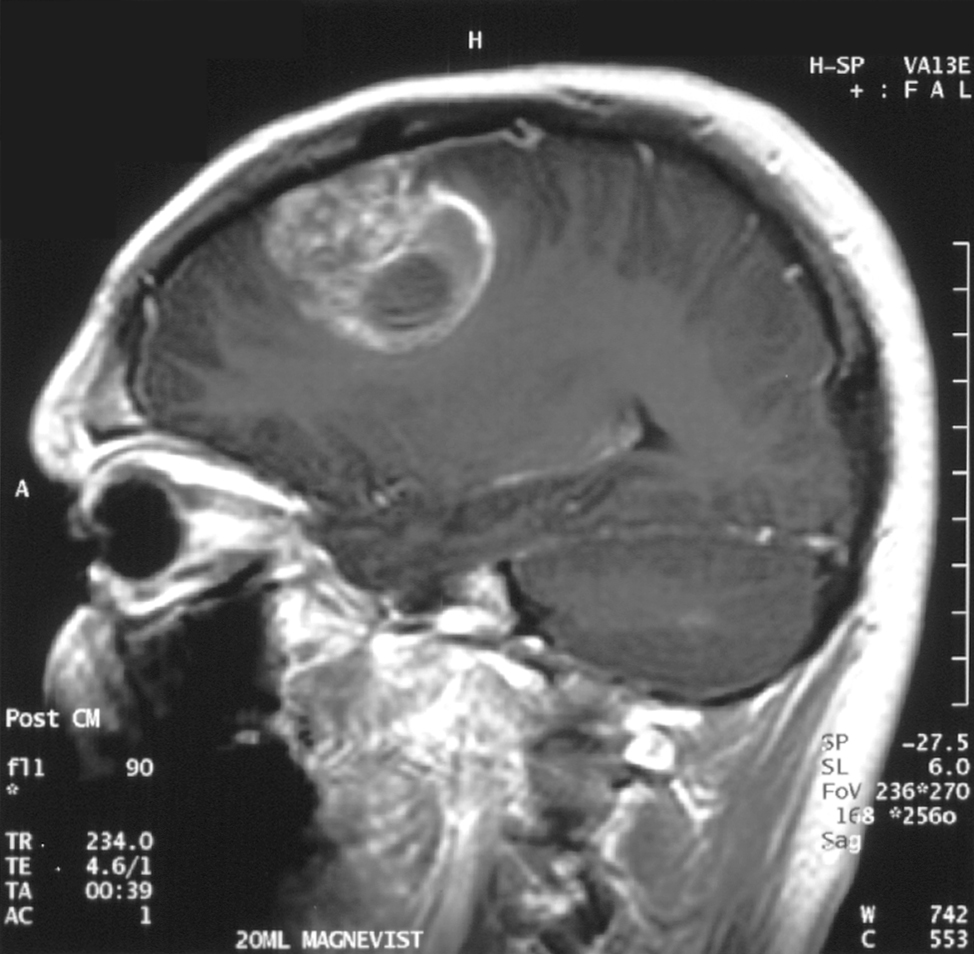

An interdisciplinary team of researchers from the University of Notre Dame is investigating the mechanisms of neuron death caused by chronic compression – such as the pressure exerted by a brain tumour – to better understand how to prevent neuron loss.

“The impetus for this project was to figure out those underlying mechanisms. In cancer research, most researchers are focused on the tumour itself, but in the meantime, while the tumour is sitting there and growing, it’s damaging the organ that it’s living in,” said Meenal Datta, the Jane Scoelch DeFlorio Collegiate Professor of Aerospace and Mechanical Engineering at Notre Dame and co-lead author of the study. “We fully believe that these growth-induced mechanical forces of the tumor as it expands is part of the reason we see damage in the brain.”

As an engineer who leads the TIME Lab, Datta studies the mechanics of tumors and the microenvironment, specifically for glioblastoma, an incurable brain cancer. She had found in prior work that tumors damage the surrounding brain. But to understand the mechanisms by which tumors kill neurons from compression alone, Datta needed a “hardcore neuroscientist.”